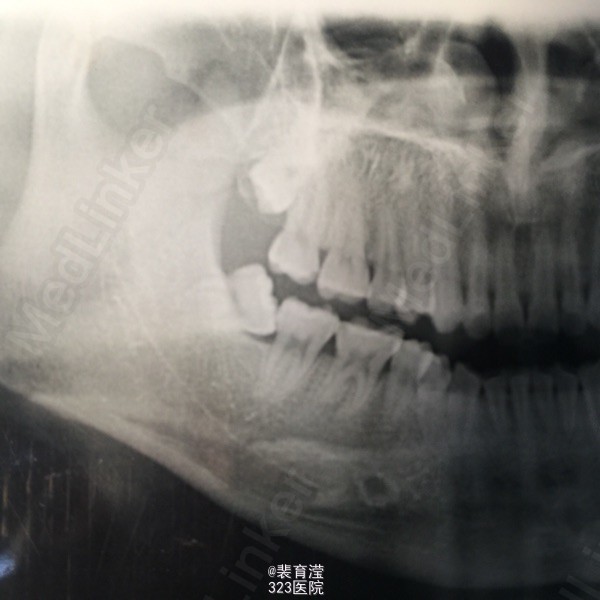

检查:右侧上颌第一磨牙,颊部前庭沟底,直径1.5mm 囊肿,探不适,波动感。 右下第三磨牙 近中阻生

诊断:异物囊肿 右下第三磨牙阻生 处理:1.局麻下切除异物囊肿,缝合,止血。 2.右下第三磨牙局麻下 拔除 搔刮牙槽窝 止血。

随访:口服消炎药 ,止疼药后无不适,一周后拆线 讨论:阻生齿拔除 先去处阻力。